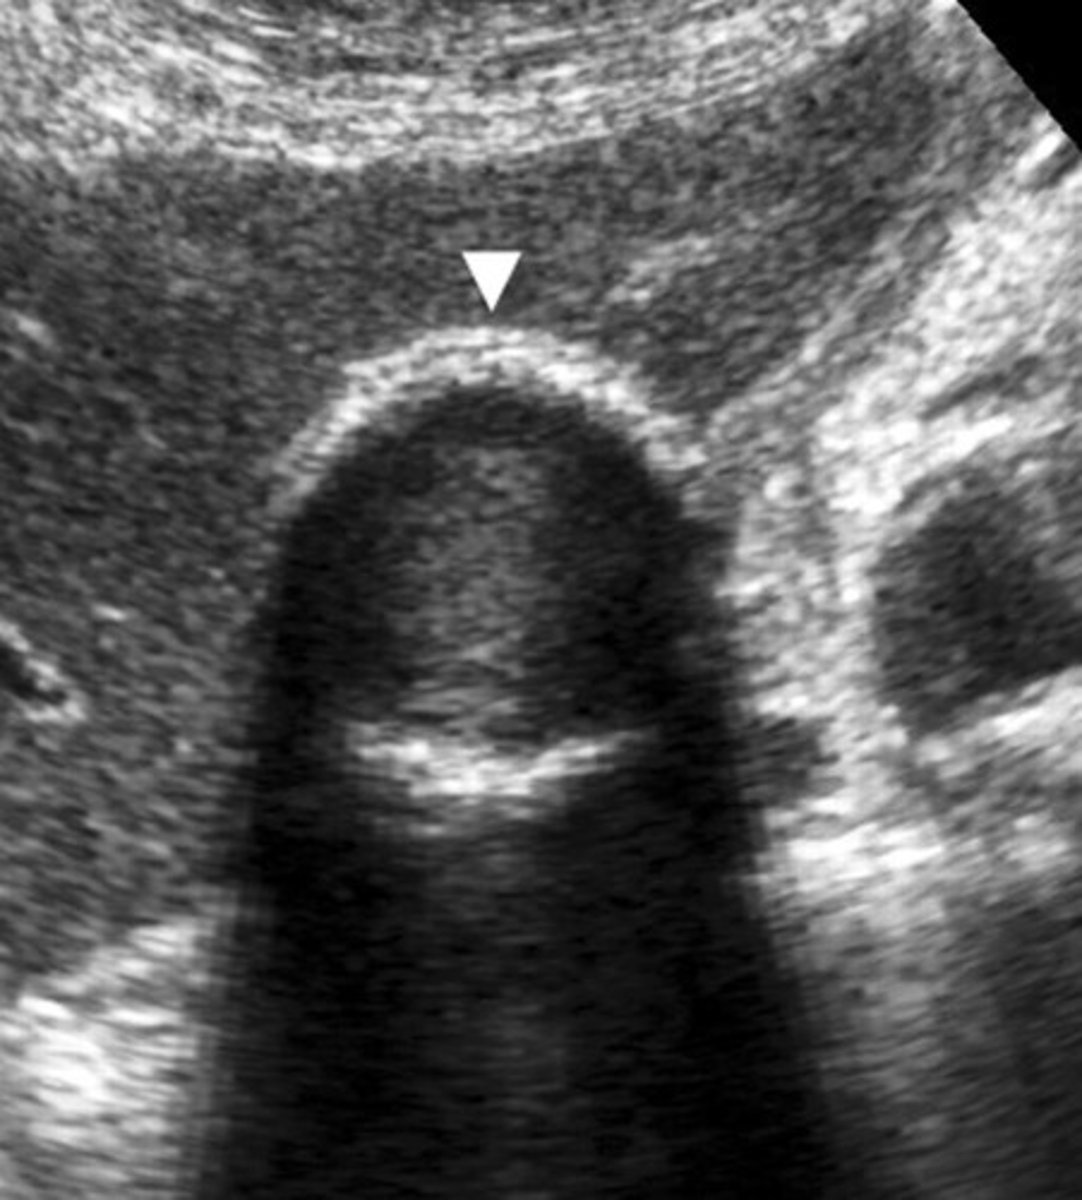

adenomyomatosis

- a hyperplastic change in the GB wall (polyp projection, no stalk)

- may be focal or diffuse

- the condition of glands within the muscle of the gallbladder

- muscular layer becomes thickened producing diverticuli or tiny pockets called Rokitansky-Aschoff sinuses

*the sinuses contain cholesterol crystals that produce comet-tail artifact seen protruding into the GB from the ANTERIOR wall*

Adenomyomatosis clinical symptoms and sonographic findings

-asymptomatic

-small, echogenic foci seen in GB wall with comet tail/reverberation artifact seen posterior

-no movement with change in patient position